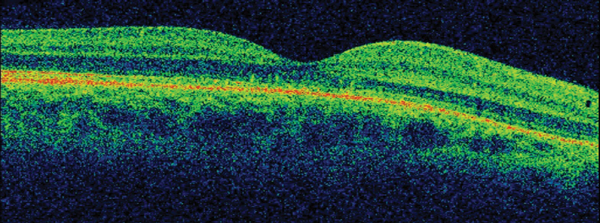

On ocular examination, visual acuity was 6/6 in both eyes (BE). Anterior segment and intraocular pressure were normal. Fundal assessment revealed a characteristic lesion in the macular area in the right eye shown in Figure 1a. Figure 1b shows the corresponding optical coherence tomography (OCT) image of the lesion. Left eye (LE) fundus was unremarkable.

Figure 1b: RE OCT.

1. Figure 1a shows an area of retinal pigment epithelium changes associated to a surrounding well-defined round area of serous macular elevation. The fluid is occupying the space between the photoreceptor layer above and retinal pigment epithelium (RPE) below called subretinal space. Given the young age of the patient, the unremarkable medical history but the underlying stress, and the clinical features the most likely diagnosis would be central serous retinopathy (CSR). The most accepted current theory to explain the pathophysiology of CSR is a combined dysfunction of both choroid and RPE resulting in focal choroidal hyperpermeability and eventual accumulation of fluid in the subretinal space.